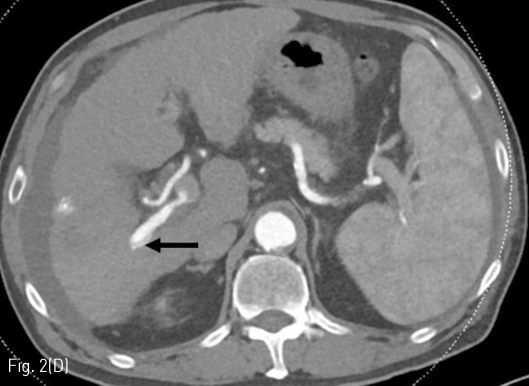

Fig 2D

Follow up liver CT 11 months after RFA. (A-D) There is a connection (arrows) between a branch of the S7 segmental hepatic artery and right posterior portal vein.

정기적 추적검사로 시행한 자기공명영상 (MRI)에서 7번 간분절(S7)에 간담도기에 저신호강도로 보이고 확산강조영상에서 고신호강도로 보이는 간암으로 의심되는 결절이 발견되어 고주파 열치료술이 시행되었다 (Fig. 1A, 1B). 10개월 후 추적검사로 시행한 전산화 단층 촬영의 동맥기 영상에서 우측 후방 간문맥이 주위 간동맥만큼 조영증강이 되는 소견을 보이고 있다(Fig. 1C, 1D). 동맥기 영상에서 간동맥과 간문맥 사이에 연결성이 보여 간동문맥단락이 의심되는 소견을 보이고 있다(Fig. 2).